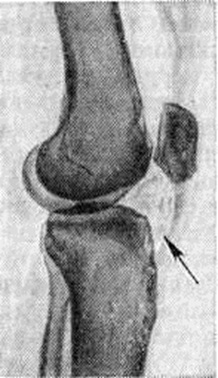

Артропневмограмма коленного сустава при болезни Гоффы: на фоне введённого в полость сустава кислорода контрастируется плотное ячеистое склерозированное жировое тело (указано стрелкой).

Клиническая картина весьма характерна. Больного беспокоят боли в суставе, «хруст» при движениях, пальпация сустава болезненна в области собственной связки надколенника; определяется выпот в суставе; при разгибании голени характерно выбухание двух валиков по обе стороны собственной связки надколенника, движения в суставе ограничены, особенно при сгибании. На артропневмограмме склерозированные жировые складки видны в виде плотного ячеистого треугольника (рисунок). Постановку диагноза облегчает наличие типичных анамнестических данных (длительная травма сустава или перегрузка его однообразными движениями).